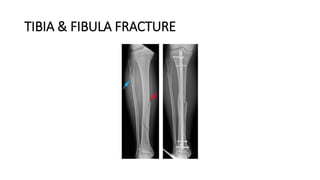

TIBIA & FIBULA FRACTURE

DEFINITION

• The tibia, or shinbone, is the most commonly fractured long bone in the

body.

• A tibial shaft fracture occurs along the length of the bone, below the knee

and above the ankle.

• It typically takes a major force to cause this type of broken leg. Motor

vehicle collisions, for example, are a common cause of tibial shaft fractures.

• In many tibia fractures, the smaller bone in the lower leg (fibula) is broken

as well.